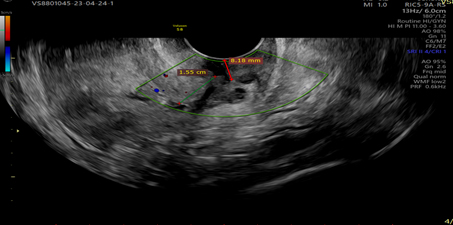

Vascular pattern: single blood vessel with or without laceration, multiple blood vessels of focal origin, multiple blood vessels of multifocal origin, scattered blood vessels(Pictures 1-6).

Picture 6.Showing tumor invasion into the cervical stroma, visualizes clear demarcation of tumor echogenicity from the cervical stroma.